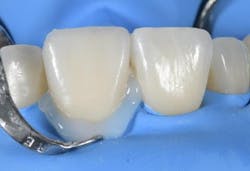

After the try-in, the veneer was etched and silanated. A single-component ceramic primer (Monobond Etch & Prime, Ivoclar) was used to etch and silanate the veneer in a single step. This eliminated the need for etching the contact surface with hydrofluoric acid. After that, the veneer was rinsed with water and dried. The tooth surface was cleaned with fluoride-free Proxyt paste and then etched with etching gel. The adjacent teeth were protected with dental Teflon tape during the procedure. After rinsing off the etching gel, the desired etching pattern became visible. Then, the adhesive (Adhese Universal, Ivoclar) was applied (figures 4–7).

I chose Variolink Esthetic LC (neutral) for the cementation procedure. Thanks to its new high-viscosity formula, the material is now even easier to handle. It can be applied with accuracy and stays in place without spreading uncontrollably (figures 8, 9). Once the veneer is correctly placed on the tooth, you can feel a slight resistance (tactile feedback). I placed the veneer using an OptraSculpt Pad, performed a brief tack cure, and then removed excess cement with dental floss (figures 10, 11). This was followed by final light curing (Bluephase PowerCure, Ivoclar). To prevent the formation of an oxygen inhibition layer at the restoration margins, I covered the cementation joint with glycerine gel Liquid Strip before the final cure (figures 12, 13).